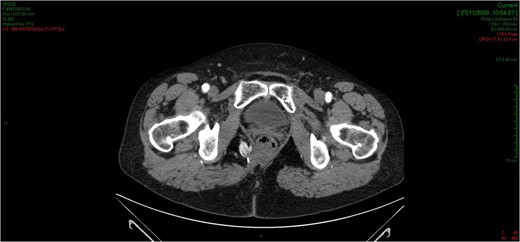

The patient was discharged home on fifth post-operative day, and she did not receive any further therapy. In December 2008, she presented an hypo-dermal recurrence in the same area demonstrated with CT-scan (Fig. 10). The patient underwent to surgery for complete resection of the recurrent lesion. After 1 year, a Magnetic Resonance (MRI) demonstrated the surgical scar without sign of recurrence. After a 7-years follow-up the patient is still alive, without any clinical or radiological evidence of recurrence, she did not need any chemotherapeutic or radiotherapeutic treatment.

The CT scan demonstrates an hypodermal recurrence of the lesion in the side of resection marked with a metallic clip.